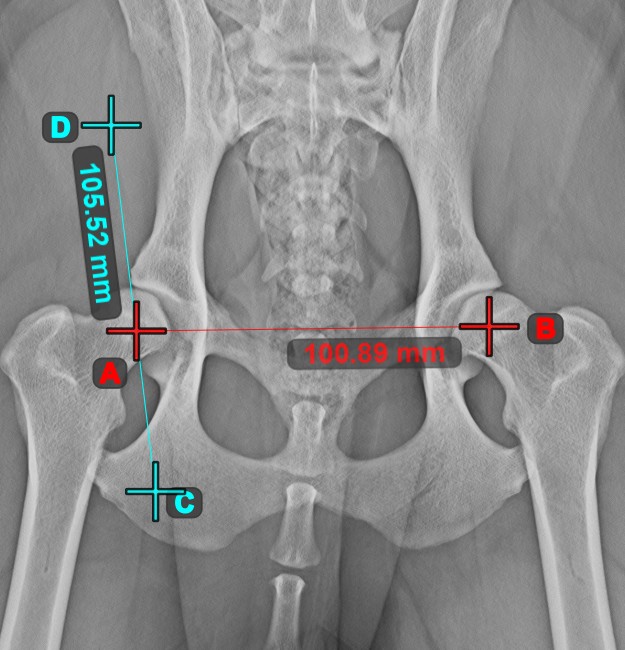

Mark simple points on the image using the Measurement Point tool. Each point is assigned with a letter for better identification.

Modify the position of the points on the image by using the Select/Move Item tool. Select the point by using the assigned mouse button of the tool, and then move it freely anywhere on the image.